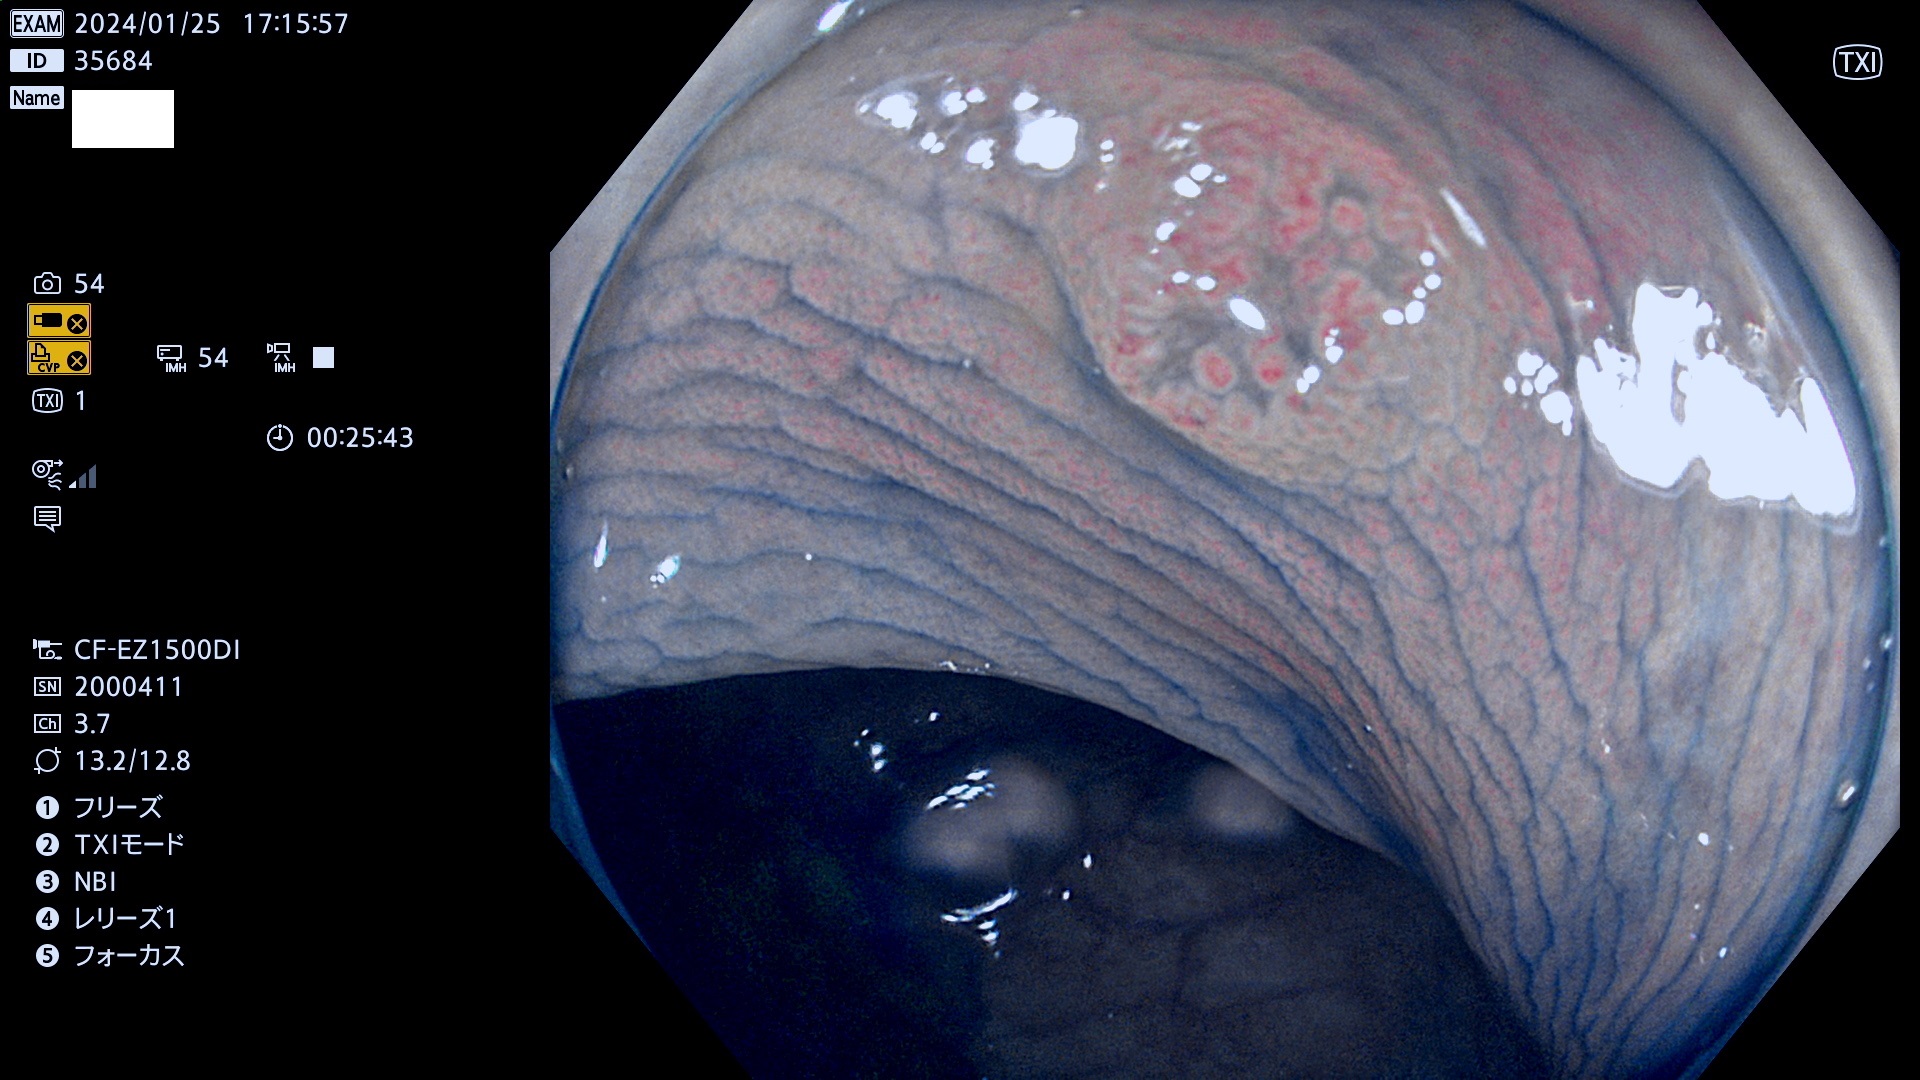

表面型腺腫(Flat Adenoma)の中で、完全に平坦な物をUb、陥凹している物をUcと呼びます。平坦隆起型(Ua)よりも、発見が難しく危険な病変です。

専門的)Uc=De Novo癌? 内視鏡の解像度が低かった時代、このような説もありました。しかし今日の高精度内視鏡では良性の微小なUc型腺腫が日常的に見つかります。私見ですが「Ucこそが多段階発癌(Adenoma-Carcinoma Sequence)のMain Route」と考えます。

毎週の検査(木・金・土・日)に発見されたUb、Uc型・腺腫を、その週の日曜の夜にUPし1週間、提示します。

抽出の対象期間 2024年1月25日(木)〜1月28(日)の4日間(40件の検査)9件